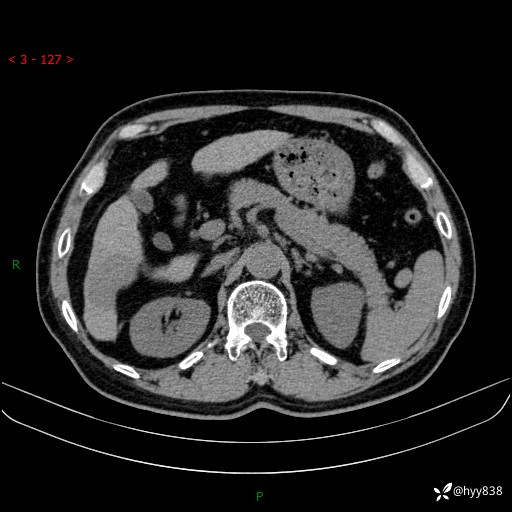

增强动脉期